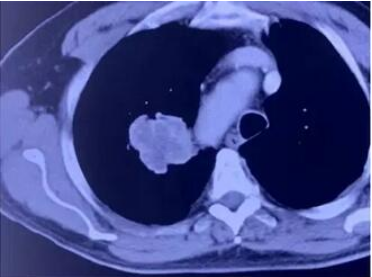

牛立志教授用2.0的微波针,穿刺到肿瘤中心,十分钟就将肿瘤消融掉了。消融后,可以看到肿瘤被烧死,同时看到毛玻璃样改变。

整个过程,病人没有任何出血发生,术后也没有咳血,全程“零出血”。这也证明了采用微波消融是一个正确的选择。